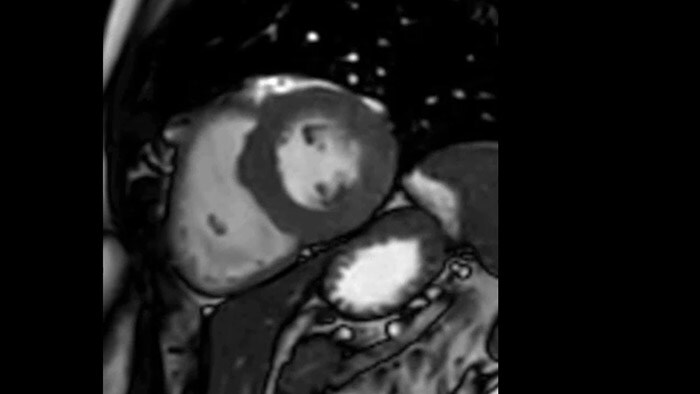

A utilidade diagnóstica e prognóstica da RM cardíaca está aumentando. Avalie a anatomia e a função do coração, usando aquisições cine; obtenha informaçõe sobre perfusão e viabilidade do tecido cardíaco; visualize edema potencial com sequência de sangue preto; acesse e até quantifique a caracterização tecidual com CardiacQuant.